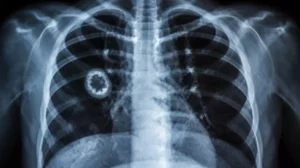

- Small Cell Lung Cancer

Small cell lung cancer arise from center of lungs and it produce